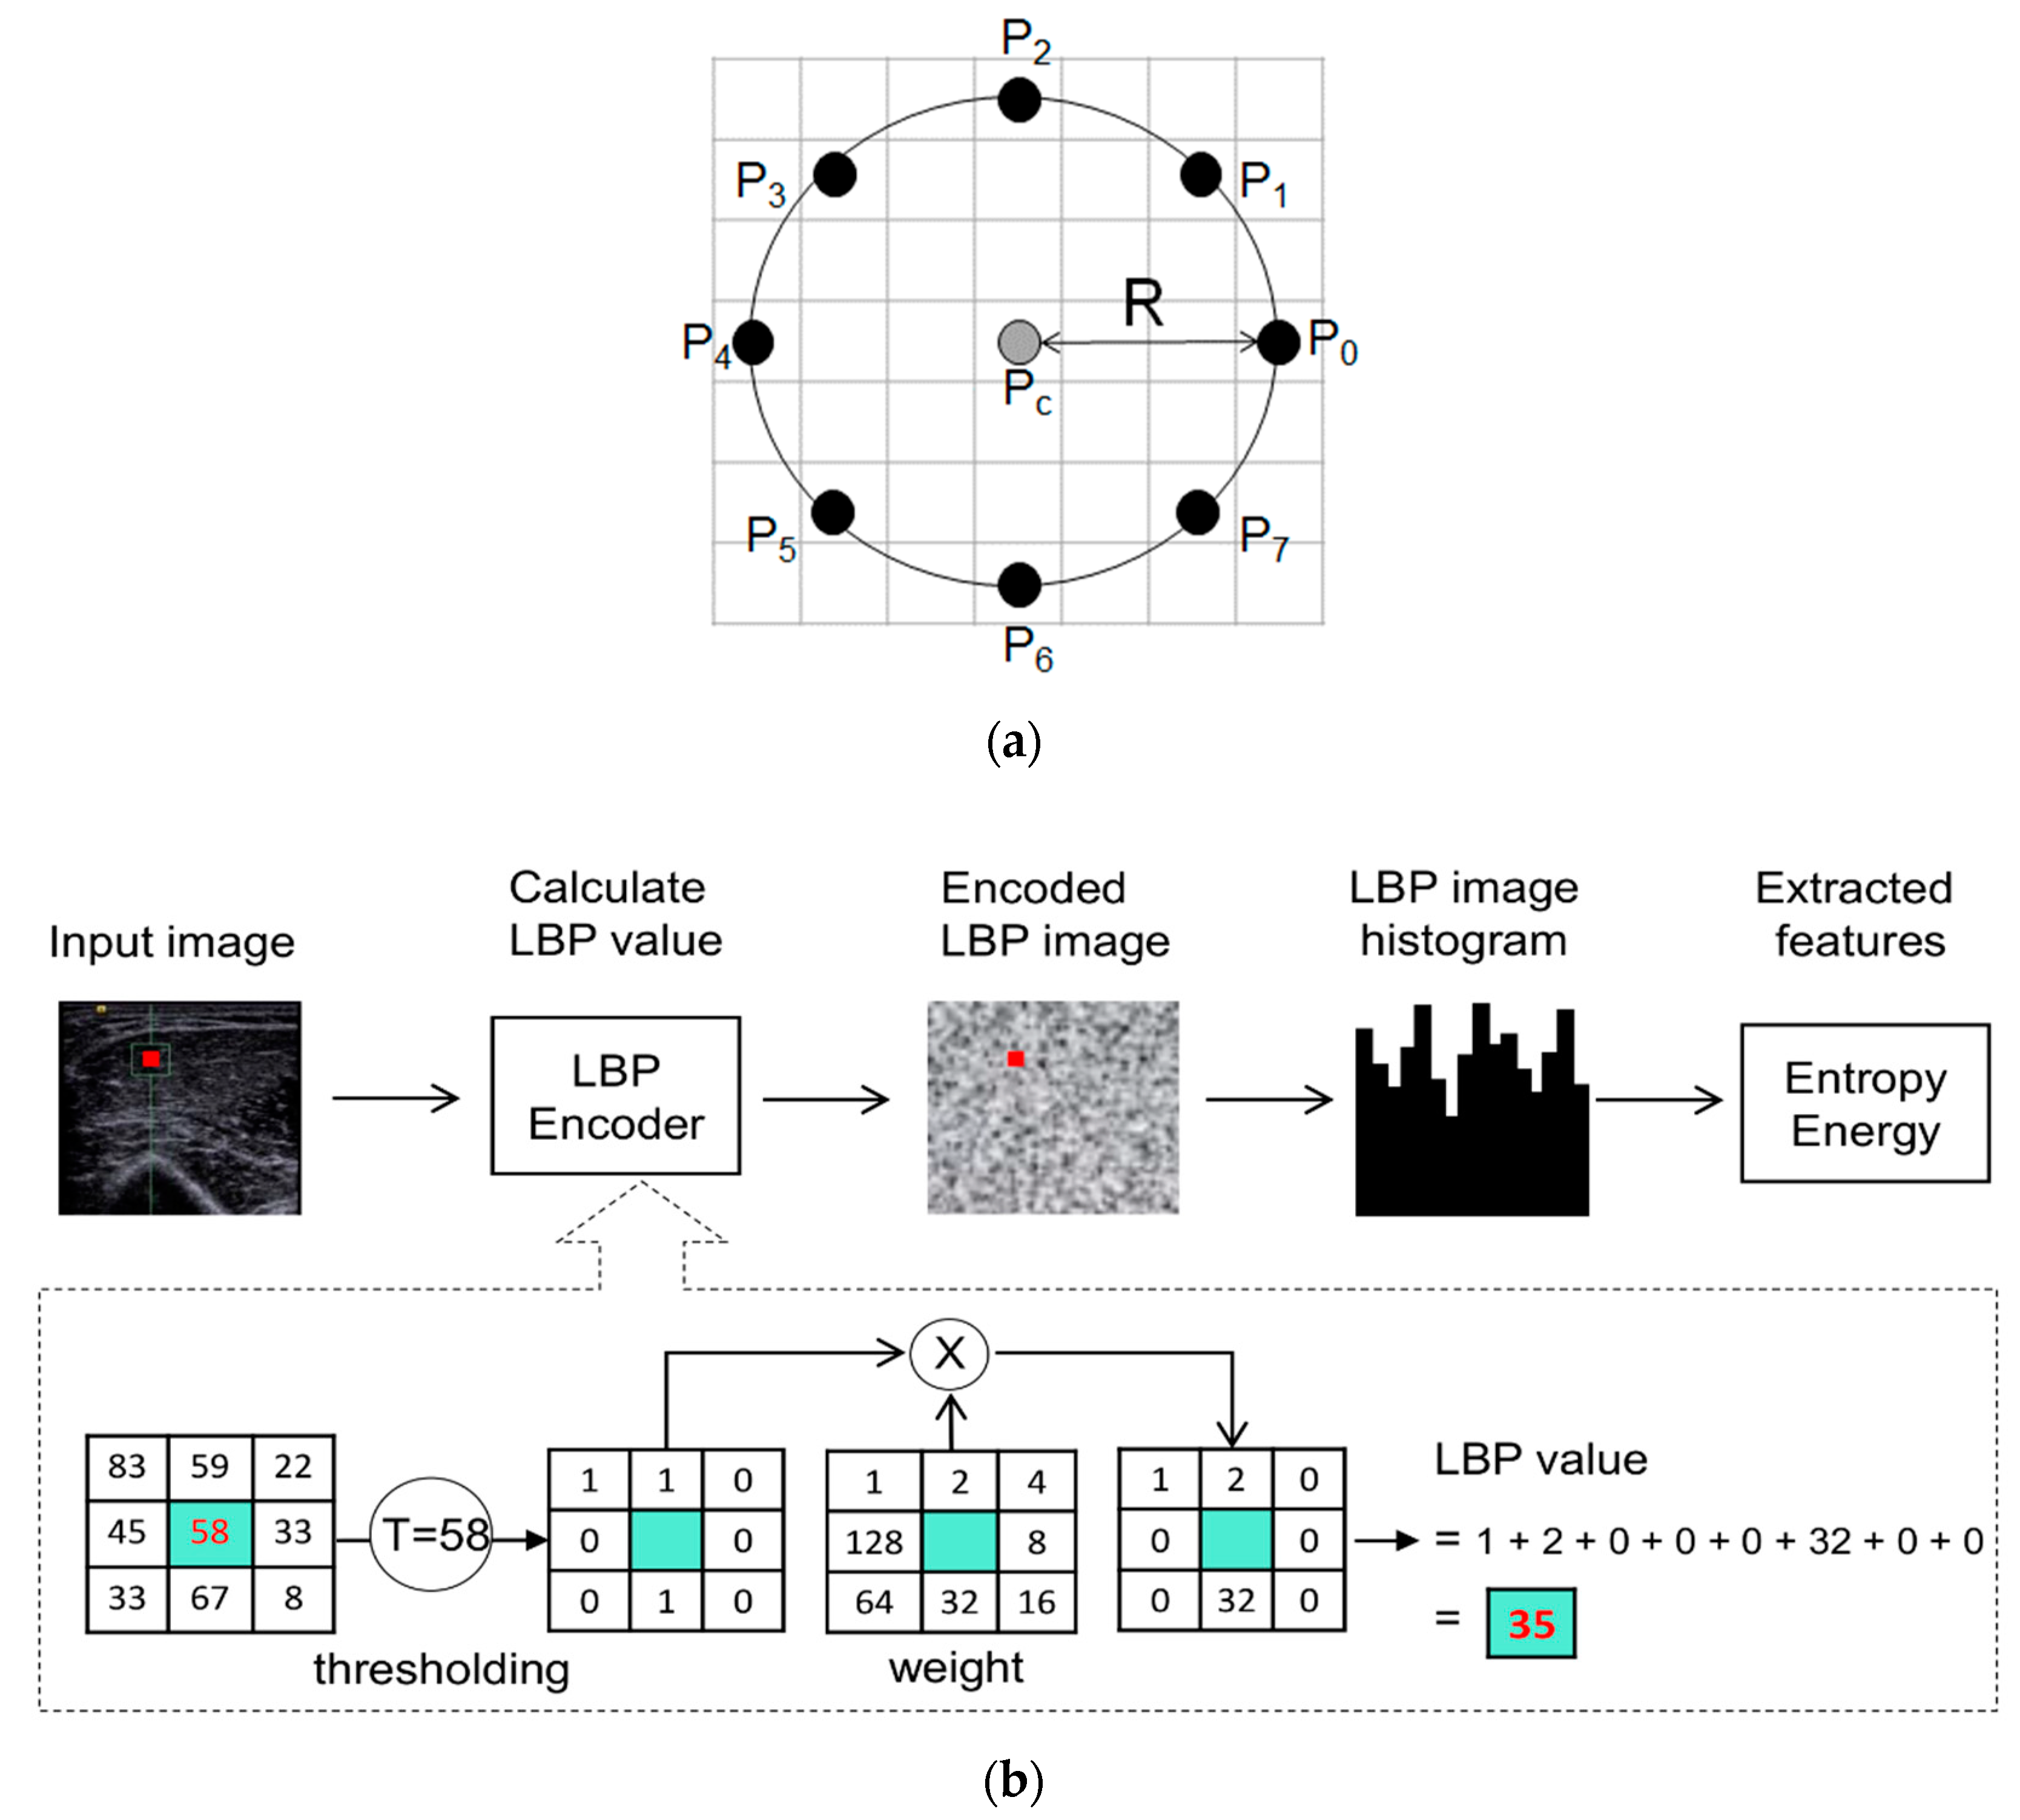

2.4. Image Processing